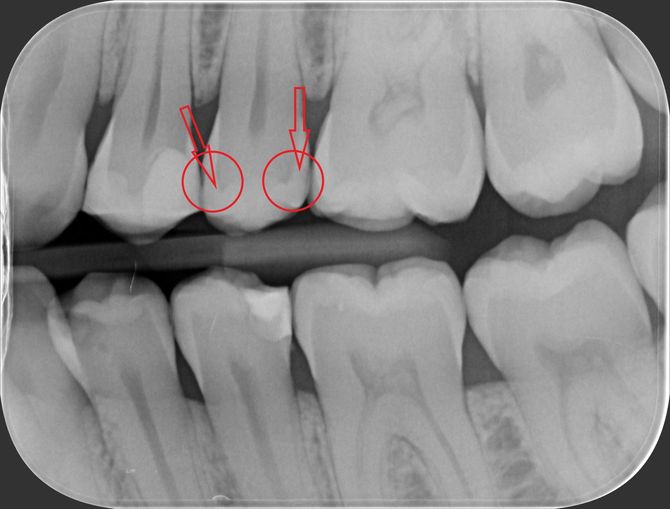

Viene presentato un caso in cui si evidenzia la presenza di carie mesiale e distale su un 25 (secondo premolare superiore di destra) attraverso l'analisi radiografica. Si deve sottolineare la difficoltà di metterne in risalto e di determinarne l'estensione solo mediante la radiografia. Nella fotografia successiva, l'entità e l'estensione della carie appaiono notevolmente superiori a quanto potesse essere dedotto dalla sola radiografia. Si mostra poi la cavità ripulita dalla carie, evidenziando la perdita di tessuto dentale causata da essa. Infine, si presenta l'otturazione appena completata, con i segni della cartina da articolazione ancora visibili, utilizzata per verificare l'altezza della cura, che richiederà successivamente un ulteriore rifinitura e lucidatura.

Un particolare utilizzo di due fasci laser e di un sensore che trasforma la transilluminazione in immagine visibile sul monitor del computer trova un utilizzo anche nella diagnosi della carie qualora l’immagine radiografica risulti dubbia o non dirimente di lesione cariosa. Ecco un esempio in cui radiologicamente si vede un’immagine non chiaramente rapportabile ad una carie come indicato dalle frecce nella radiografia a fianco. Con l’ausilio del laser si riesce ad evidenziarne completamente i limiti e la grandezza come visibile dalle due immagini e dalle frecce che indicano la carie. Tuttavia, per correttezza, va spiegato che l’efficacia di questa indagine può essere effettuata solo in determinate circostanze cliniche e che le radiografie risultano sempre necessarie.